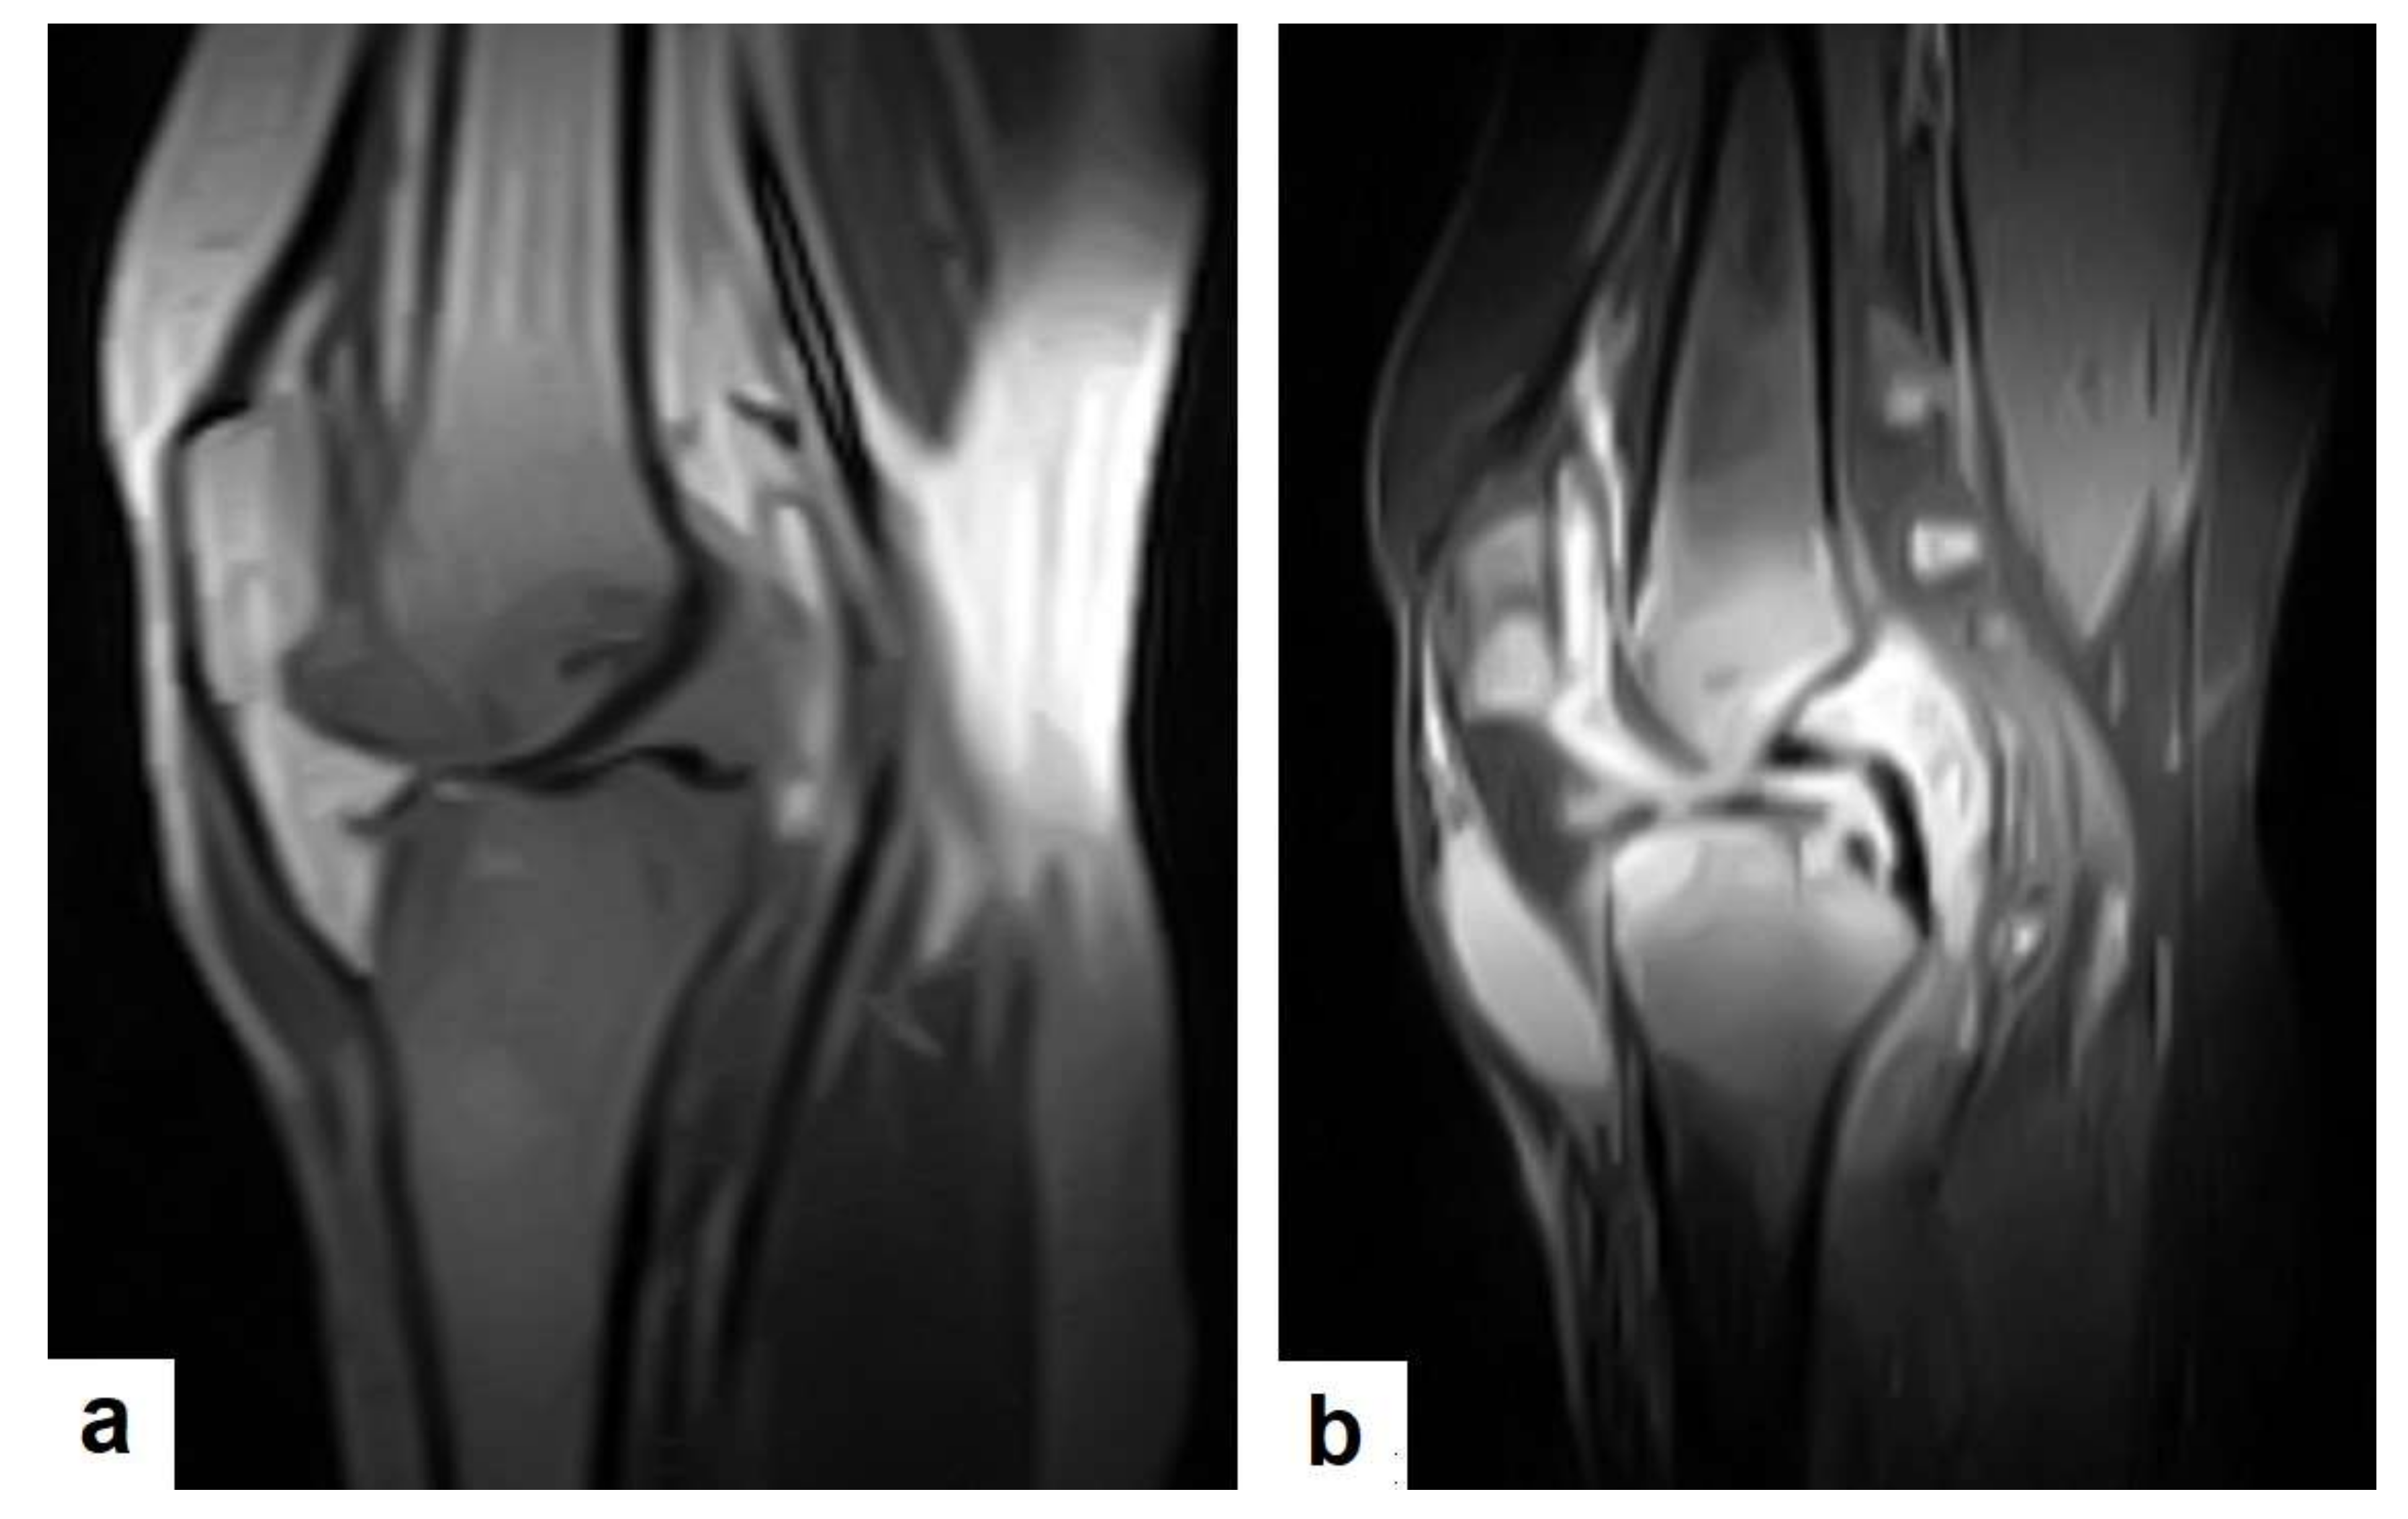

2.7. Musculoskeletal (MSK) TB

TB can affect any part of the musculoskeletal (MSK) system, and symptoms of TB may be insidious, causing TB not to be considered. CT and MRI imaging modalities can bring suspicion to TB diagnoses [57]. MSK TB has a wide range of radiological features that can mimic many pathologies all over the body. However, radiological assessment is often the first step in the diagnosis of MSK TB [58]. The most common type of MSK TB is tuberculous spondylodiscitis (Potts disease), which accounts for 50% of MSK TB [57,58] (Figure 18 and Figure 19). Osteoarthritis TB affects joints or bones. It usually affects long weight-bearing bones and sometimes affects the ribs. Articular TB usually presents as monoarthritis in the knee (Figure 24) or the hip joints. However, sacroiliac, and sternoclavicular joints are also sometimes affected. The predilection of TB to affect the vertebrae and the large joints is due to the rich blood supply to the vertebrae and the growth plates of the long bones [59]. TB arthritis presents as a slow progressive destructive monoarthritis, so the diagnosis is delayed due to the indolent onset and low clinical suspicion [60].

On medical imaging, TB may initially show soft tissue swelling and later progress to periosteal thickening, osteopenia, periarticular bone destruction, and cold abscesses, and fistulae may develop in late cases. MSK TB is a differential diagnosis of a wide bone lesion. At the early stages, it is often misdiagnosed as traumatic lesions, degenerative joint disease, gout, pseudo gout, rheumatoid arthritis, or pigmented villonodular synovitis. High suspicion of TB is required, and a final diagnosis can be carried out by using arthrocentesis and a mycobacterial culture; in addition, a synovial biopsy is often needed [59,60].

Figure 24. Knee TB in a 45-year-old patient with proved case of knee TB infection. Selected sagittal MRI images of (a) T1-weighted image and (b) T2-weighted image show extensive oedema of the articular surfaces of the knee, appearing as low signal intensity on T1 and high signal intensity on T2 with diffuse synovial thickening and large bone erosions (arrow heads), with mild joint effusion and a prepatellar pocket of fluid collection, which appear as low signal intensity on T1 and high signal intensity on T2. In addition, multiple enlarged popliteal lymph nodes were present.